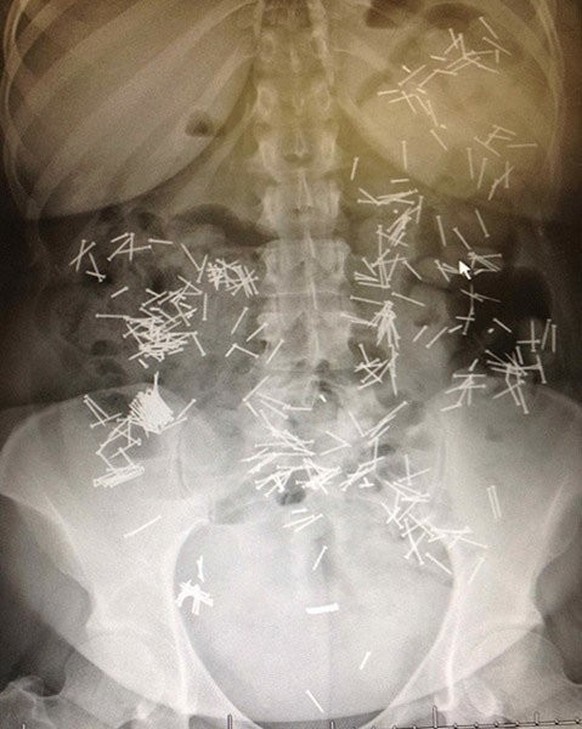

Des p'tits clous, des p'tits clous, toujours des p'tits clous...

Oui, je sais, c'est des p'tits trous.